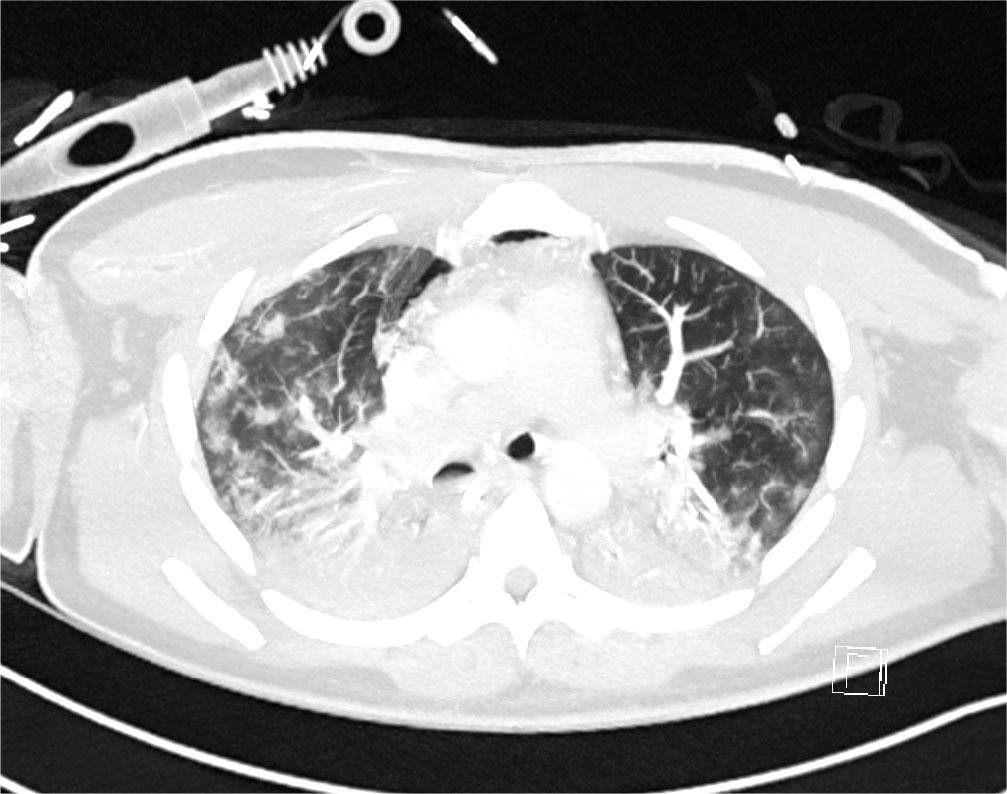

Initial blood tests on transfer demonstrated raised inflammatory markers; CRP 193, White cell count of 20.3 with a predominant neutrophilia. Haemoglobin12.0g/L, platelet count 496×109/L, creatinine 100umol/L, total protein 65g/L. ALT 112 IU/L, ALP IU/L, GGT 226 U/L, albumin 28g/L, total bilirubin 7umol/L. CK was unremarkable at 252 (ref range 44–272). A computed tomography (CT) thorax on transfer to our facility showed extensive bilateral consolidation and surrounding nodular ground glass opacification, in keeping with multi-lobar pneumonia (Figure 1). A bedside echocardiogram was essentially normal. Extensive microbiological investigations including sputum, blood, urine and broncho-alveolar lavage (BAL) culture for bacteria, mycobacteria and fungi, respiratory viral PCR from throat swab and BAL, legionella and pneumococcal urinary antigen yielded no positive results. There was no history of exposure to licensed medications or illicit drugs or factors known to cause lung disease. The presentation was one of severe Type 1 respiratory failure but notably there was no evidence of multi-system organ failure or hemodynamic compromise and hence was an unusual presentation for the initial working diagnosis of CAP with ARDS.

CT Thorax on Day 2 of admission showing extensive bilateral consolidation and surrounding nodular ground glass opacification, in keeping with multi-lobar pneumonia